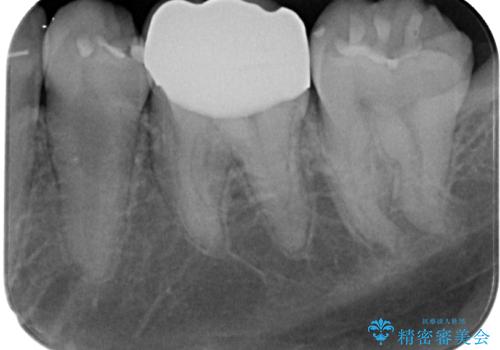

- 当院で矯正治療を終えて、左下が虫歯になっている気がするとのことで来院された患者様です。レントゲン検査の結果、コンポジットレジンによる修復箇所が複数行われており、詰め物の下に虫歯を認めました。